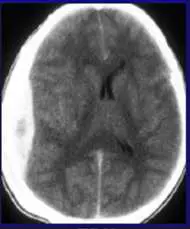

一位創傷性腦傷病患的電腦斷層影像如下圖。根據此圖,此病患有以下何種腦部出血?

本題 CT 影像(腦部軸位平掃,non-contrast axial CT)所見:

- 左側顱骨內板旁可見一處凸透鏡形(biconvex / lenticular shape)高密度(hyperdense)病灶

- 病灶邊界清楚,呈雙凸面向內的透鏡狀,緊貼顱骨內板

- 病灶不跨越顱縫線(suture lines)

- 周邊腦組織有局部受壓跡象,中線結構輕度向右偏移

- 無廣泛性蛛網膜下腔或腦室內積血

影像印象:左側顱骨內板下方凸透鏡形高密度病灶,最符合**急性硬膜外血腫(epidural hematoma, EDH)**的典型 CT 表現。